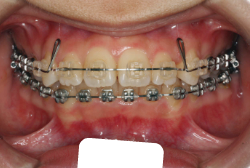

「乳歯が生え替わらない」という主訴で来院したケースです。 診断の結果、「左上永久犬歯が第一小臼歯後方上部に埋伏しているため、左上乳犬歯が晩期残存している症例」と判明しました。

このような症状の場合は、手術で埋伏している永久歯に金具を取り付け、矯正装置で牽引する必要があります。同時に凸凹の解消と前突した前歯を内側に入れるために上下左右の小臼歯を抜歯させて頂くことといたしました。

この方の場合は、マルチブラケット装置にて治療を開始し、治療期間2年3ヶ月で終了しました。犬歯の牽引距離が非常に大きかったため当院の平均治療期間よりも大幅に期間がかかりましたが、埋伏犬歯を完全に正しい位置まで誘導することができました。同時に 前歯の前突と配列の凸凹も解消しました。